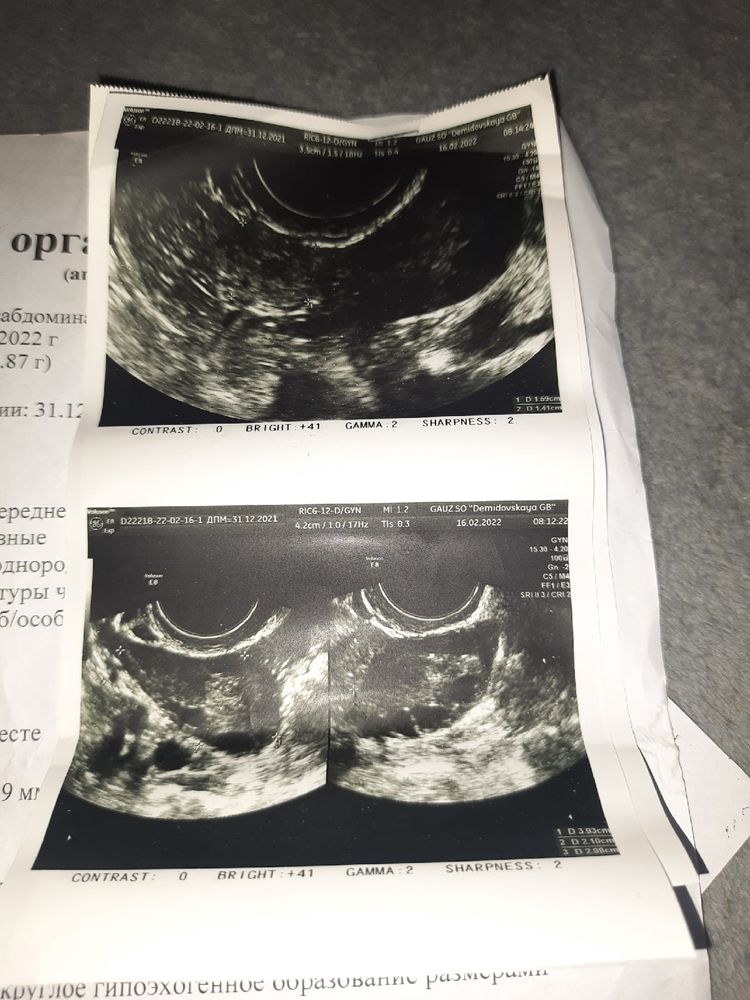

Замершая беременностьНесколько дней назад писала сюда про странную ситуацию тык. в этот же день сдала хгч, пришёл результат 79,4 . Меня сразу кольнула мысль что мало, но надежда умирает последней. Продолжаю делать тесты, а динамики то нет.(знаю динамику по тестам не смотрят, но я знаю ,что тесты должны становится ярче , у меня всегда так и было.)14.02 сдаю повторный хгч ,приходит результат 118 и тут становится понятно, что ничего хорошего ждать не стоит, но сердце верит в чудеса. Утром 15.02 не выдерживаю и снова бегу сдавать хгч ,в этот же день начинает болеть в правом боку. Срочно пишу своему врачу ,она договаривается с узистом ,чтобы с утра срочно меня приняли, встаю с утра, а у меня пошла кровь. Тут же пришёл хгч и он уже был 84,4 ,то есть за сутки упал на 30 процентов. В тот момент я боялась только внематочной. Еду на узи и у меня таки находят там что то не хорошее

Захлёбываясь в слезах бегу в стационар. Жду врача, а справа продолжает болеть. Врач посмотрел меня и решил пока не вскрывать с таким маленьким хгч, тем более он падает. Написала сдать хгч и сделать ещё узи. На следующий день 17.02 сдаю хгч, приходит 42,2 ,то есть упал ещё. Всё это время боюсь ,что лопнет труба и меня не успеют спасти.(боюсь оставить сына без матери). 18.02 иду на узи ,внематочную не находят ( искали долго, я сама на прошлом узи видела это образование и два врача видели)

. По узи картина начала цикла, с врачом пришли к выводу что это выкидыш на малом сроке. Матка уменьшилась. Тест до сих пор с //,конечно уже не такой яркий. Так обидно и горько мне, плачу, оплакиваю своё дитя. Я так о нём мечтала, ждала его. Если бы не сын, сошла бы с ума.